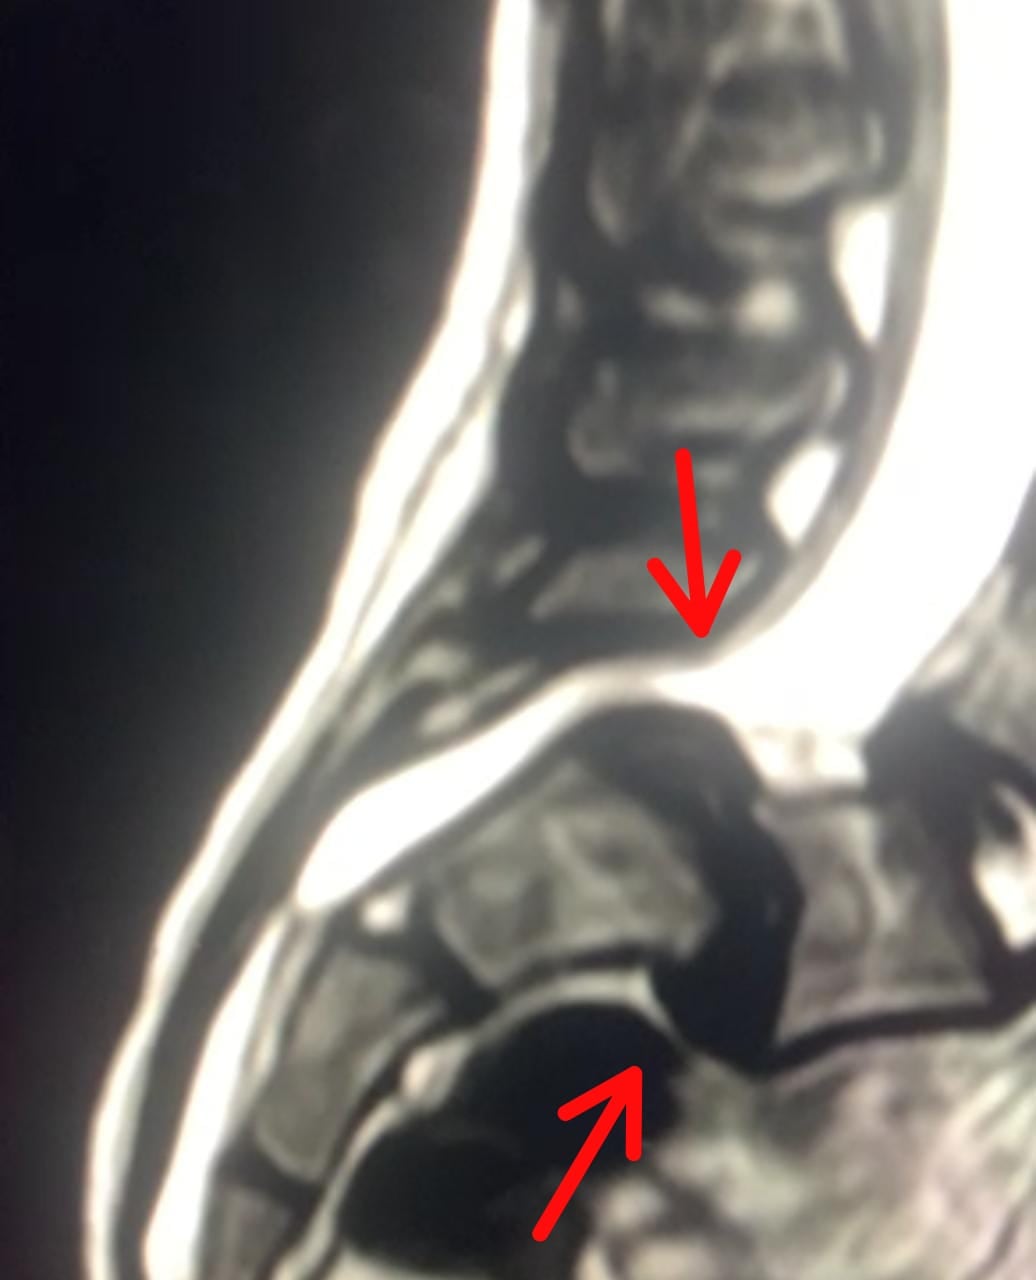

No obstante, su salud se agravó en mayo, cuando la estudiante de sétimo año fue diagnosticada por el neurólogo Ricardo Murillo con espondilolistesis, una afección en la cual una vértebra de la columna se mueve fuera de la posición adecuada. A esto se le suma una fractura en su vértebra L5 y el inicio de desplazamiento de la L4, explicó Murillo a La Nación.

La espondilolistesis es un síntoma de la enfermedad base que padece Sofi, la hiperlaxitud articular. Según detalló el neurólogo, el movimiento de las vértebras compromete la integridad de la médula espinal de la niña, pues dicho movimiento pellizca los nervios y provoca un gran dolor, al tiempo que amenaza las posibilidades de que la joven colegial vuelva a caminar, correr y jugar.

La enfermedad que padece Sofía, agregó, se ve agravada por el rápido crecimiento que se da en adolescentes. “Ella tiene de enero a hoy un deterioro significativo, no solo por el dolor, sino porque tiene radiculopatía, es decir, algunas raíces nerviosas ya muestran daños y eso se manifiesta con debilidad en las piernas, torpeza para caminar e incapacidad de mantener una postura”, detalló el especialista.

De acuerdo con Murillo, dicha cirugía deberá ser realizada por al menos tres médicos cirujanos con experiencia en intervenciones similares. Él ha realizado varias operaciones por espondilolistesis, pero nunca en una menor de 13 años. A Sofía deberán colocarle tornillos para fijar y acomodar las vértebras que se han desplazado y comprometen su médula.